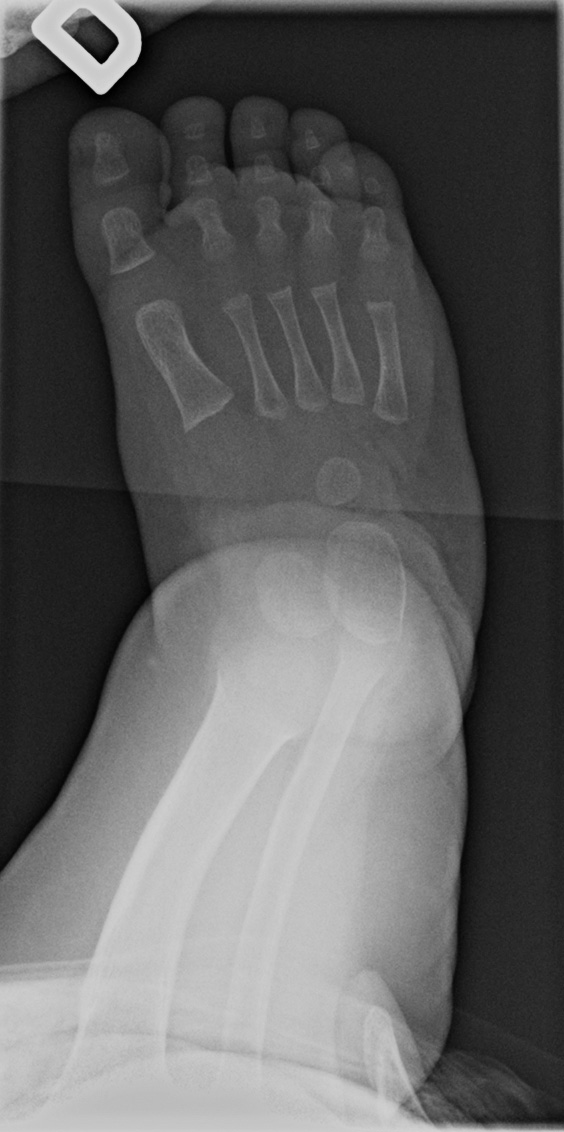

0-hour-old male:

Feet deformity.

Clubfoot

On the right side, the anteroposterior talo-calcaneal angle (Kite's angle) is decreased to 7° (normal between 20 and 40°). On the lateral view of Turco, the talo-calcaneal angle is 30° (normal over 35°). In short, on the anteroposterior view, the talus and calcaneus are more parallel than expected (normaly they are diverging).

On the right anteroposterior view, the talus-1st metatarsal angle is measured at -7° (normal between 0 and 20°). The 1st metatarsal is medial to the talus because of the forefoot deviation in varus and adductus.

Talus

On the left side, the talus is not ossified enough to take measurements. Global alignment, however, suggests a left club foot of similar severity than the right.